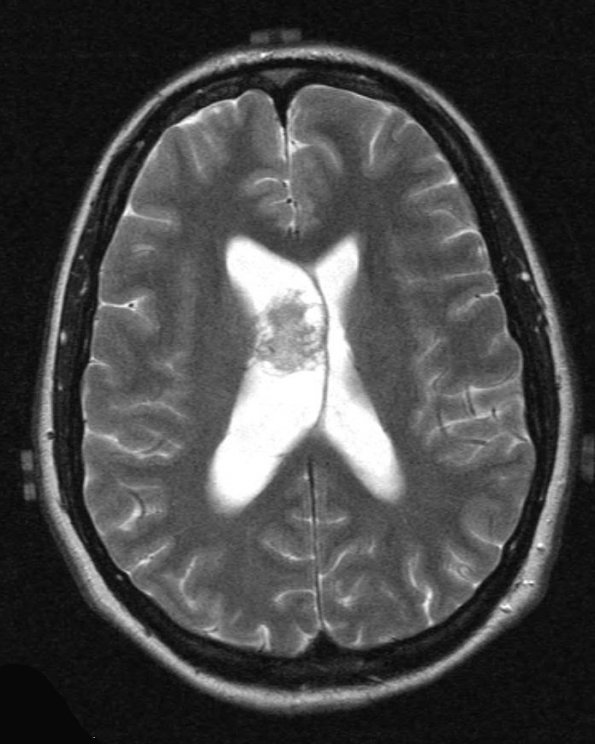

4A3 Neurocytoma, central, atypical (Case 4) T2 2 - Copy

The appearance is bubbly and nodular on T2-a weighted image.